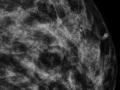

Bases físicas da mamografia